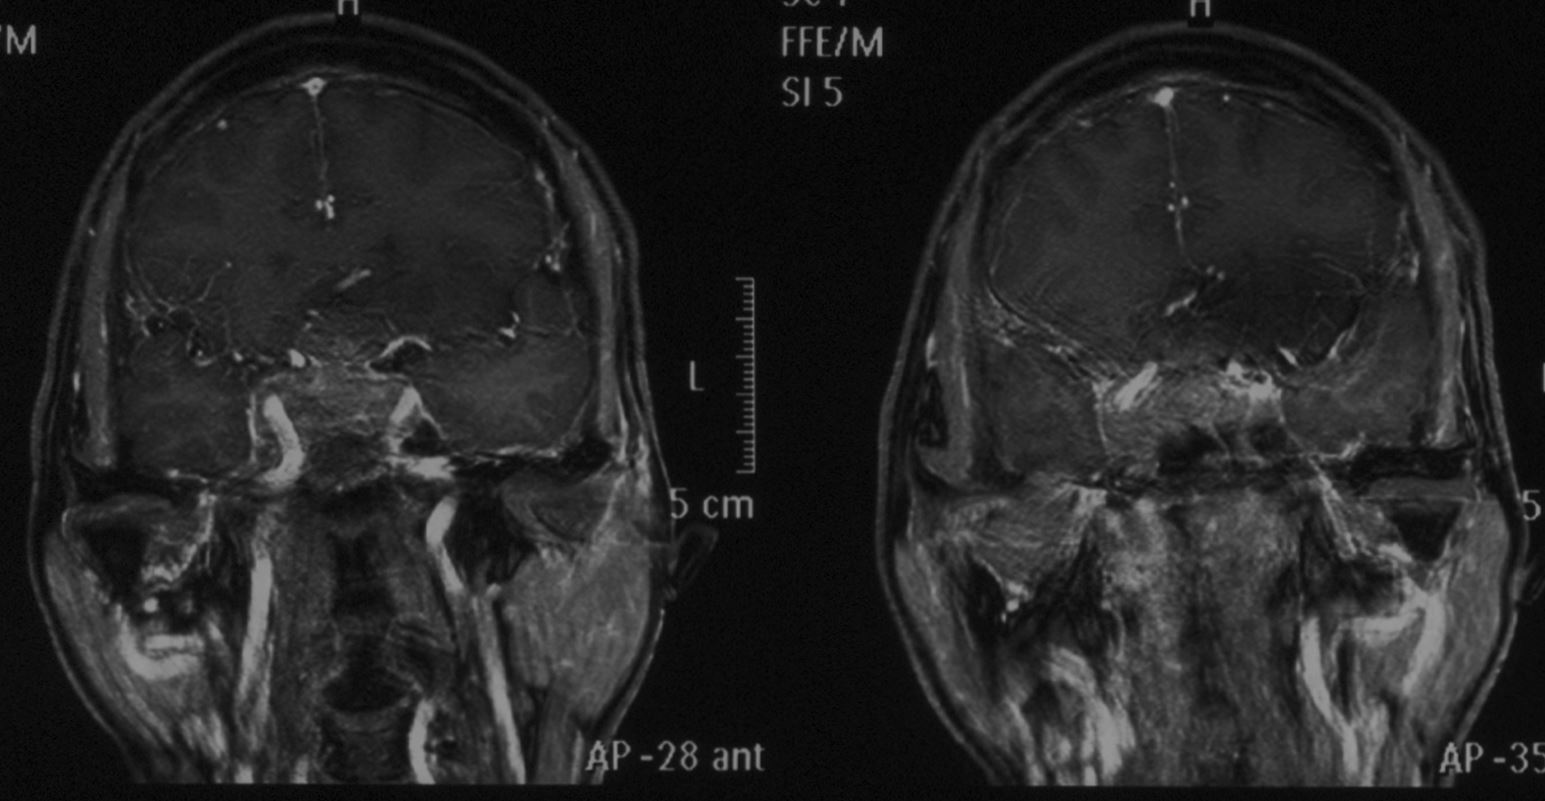

头颅MRI示:鞍区占位性病变,肿瘤大小约2*2.8cm,T1等信号,T2混杂信号,增强后部分强化。肿瘤刚突破鞍底向蝶窦生长,向上突破鞍隔向上生长,视交叉明显受压,左侧较为严重。肿瘤向两侧生长,海绵窦及颈内动脉受侵犯。垂体瘤卒中可能大。